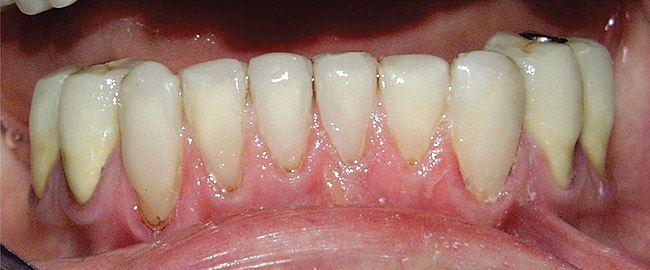

Figure  6  Erosion and abrasion in a xerostomic patient with Sjögren’s syndrome.

Figure 6